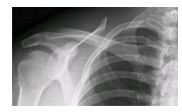

Какой сустав человека изображён на рентгеновском снимке?

3) плечевой

Решение:3) плечевой

Ответ: 3